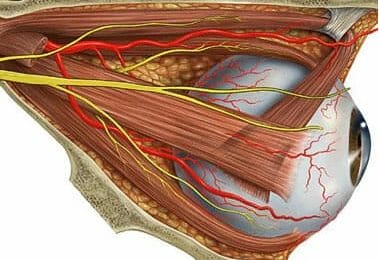

Rectus medialis

De beweging van ogen wordt verzorgd door heel kleine sp...

Onderste schuine oogspier

De beweging van de oogballen wordt bestuurd door kleine...

Bovenste rechte oogspier

De beweging van de oogballen wordt bestuurd door kleine...